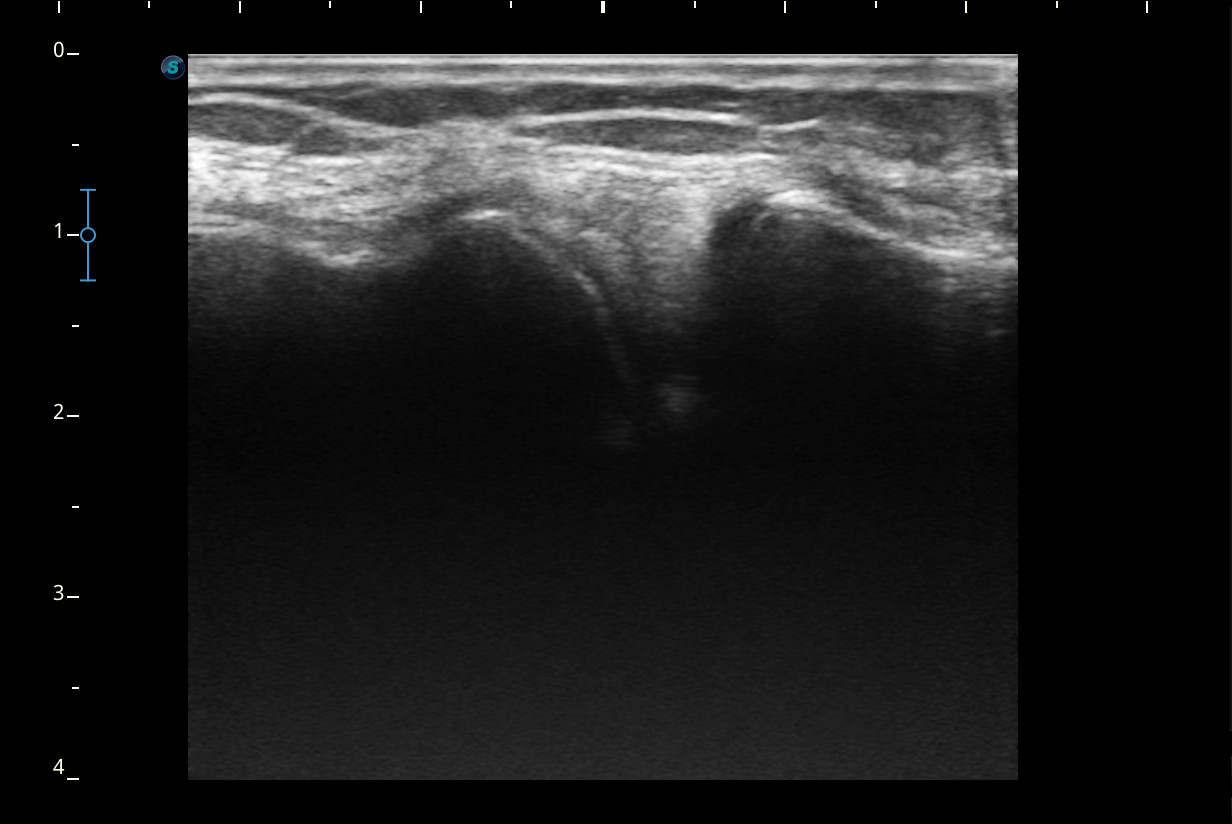

Se realiza ecografía de rodilla.

Descripción de los hallazgos ecográficos y las imágenes más relevantes para la resolución del caso

Rodilla sin derrame articular. No se aprecian lesiones en Ligamentos colaterales. Ligamento rotuliano sin hallazgos valorables. Rotura menisco interno y dudosa fisura menisco externo. Tendones rotuliano y cuadricipital normales.

Resonancia magnética confirma rotura cuerno posterior menisco interno.